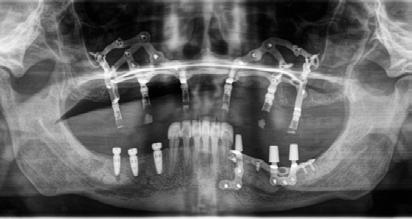

Eaglegrid: singolo intervento a carico immediato in gravi atrofie ossee

Risolvere le atrofie ossee, può essere un compito complica to per i clinici. Le richieste dei pazienti sono ormai mirate a risolvere le edentulie parziali o totali con tempi sempre più corti e con il restauro protesico in tempi corti o ancora meglio caricamento immediato degli impianti. L’implantologia, cosi definita tradizionale, ovvero con impianti endossei riesce a rispondere a queste esigenze in modo concreto nella maggior parte dei casi.

Ci sono però situazioni cliniche, in cui il riassorbimento dell’os so alveolare è troppo avanzato lasciando spazio solo ed esclu sivamente all’osso basale. Sono state proposte tecniche rige nerative, utilizzando materiali di ogni tipo. I risultati non sono tutti favorevoli a questo tipo di approccio e con una soddisfa zione dei pazienti non ottimale considerando che è necessario affrontare più interventi con tempi di guarigione lunghi e senza poter posizionare imme diatamente la protesi. Il proto collo Eaglegrid, invece riesce a

rispondere concretamente alle esigenze dei clinici e dei pa zienti. Consiste nell’espressio ne massima dell’implantologia digitale, portando una rivolu zione del campo dell’implanto logia subperiostale. Gli impianti subperiostali erano stati abban donati per le difficolta tecniche, dovute a tecnologie troppo ru dimentali. EAGLEGRID invece segue i casi a 360 gradi, inizian do la progettazione dei casi a partire dai restauri protesici con cui i clinici vogliono riabilitare i pazienti.

Viene quindi eseguita una pro tesi guida, utilizzata come dima radiologica, con cui verrà ese guito l’esame radiologico ovve ro una CBCT. La dima radiolo gica consente al team di clinici, bio ingegneri ed informatici di sviluppare la struttura dell’im pianto subperiostale da stam pare con tecnica laser melting con le corrette emergenze pro tesiche, rispettando ciò che ve ramente il clinico vuole ottene re. La precisione del manufatto, prodotto in laser melting, è quindi al centesimo di millime

tro e presenta a livello micro scopico una struttura perfetta, priva di difetti. Grazie alle tec nologie digitali, le possibilità di riabilitazione sono infinite e si può quindi riabilitare l’elemen to singolo come nel caso delle agenesie, edentulie parziali, sia nel mascellare superiore che in feriore o arcate totali. È anche possibile utilizzare in sinergia gli impianti endossei o pterigoidei nel caso fosse ne cessario.

EAGLEGRID, è stata la prima soluzione digitale italiana per la chirurgia sottoperiostale, può quindi vantare ormai un enorme numero di casi con fol low-up di 10 anni. Molti clinici da anni si affidano a Eaglegrid, per risolvere i casi di gravi atro fie con un approccio definito stress-free, considerando che viene fornito un servizio com pleto, dalla progettazione all’at to chirurgico direttamente dal team di EAGLEGRID.

Per concludere è un trattamen to che si inserisce nell’implan tologia di tipo NON endossea, che sfrutta l’intimo appoggio ad una struttura ossea nella sede sottoperiostale, piuttosto che la sua integrazione all’in terno di essa. È una metodica riservata alla risoluzione di gra

vi atrofie verticali e trasversali, dove non è possibile eseguire una implantologia endossea e dove la rigenerativa è scon sigliata. EAGLEGRID rappre senta un prodotto innovativo frutto della coniugazione della radiologia digitale accoppia ta alla produzione CAD CAM. Consente al clinico di ipotizzare la risoluzione di qualsiasi caso di atrofia anche marcata in un solo intervento, garantendo an che il carico immediato. Il pro tocollo, brevettato, è certificato secondo le più recenti direttive in materia implantare.

L’estrema flessibilità della me todica si può applicare da un singolo dente a selle come ad intere arcate sia mascellari che mandibolari. Sempre più clinici e pazienti richiedono un tratta mento con EAGLEGRID. L’alta predicibilità di risultato è uno dei motivi di successo di EAGLEGRID anche a livello inter nazionale a riprova che il den tale MADE IN ITALY, ancora una volta può essere di esempio in altri paesi.

Abbiamo rivisitato in chiave di gitale una metodica che grazie a noi sta rivivendo una nuova giovinezza ampliando di molto gli orizzonti dei trattamenti im plantari.